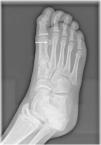

We present the case of a male adolescent aged 13 years who presented to the emergency department with pain in the metatarsophalangeal joint of the first toe of the right foot that developed after hitting the ground accidentally during a soccer game the day before. He had mild swelling at the hallux and tenderness on palpation of the joint. The foot radiograph (Fig. 1) evinced a bipartite lateral sesamoid.

Sesamoids are small pea-shaped bones embedded tendons to reinforce them and relieve the stress to which they are subjected.1 In the foot, the lateral and medial hallux sesamoid bones are located in the plantar surface of the head of the first metatarsal.2 Bipartite sesamoids are normal variants resulting from incomplete fusion during development, with an incidence of 7%–30%.1 The main differential diagnosis is sesamoid fracture, usually resulting from the forced hyperextension of the first toe, which may go undetected in some cases and cause complications such as avascular necrosis.2,3 In this case, the management was conservative, based on rest and off-loading the foot. The patient had a favourable outcome and was able to start resuming his athletic activities gradually in less than 2 weeks.